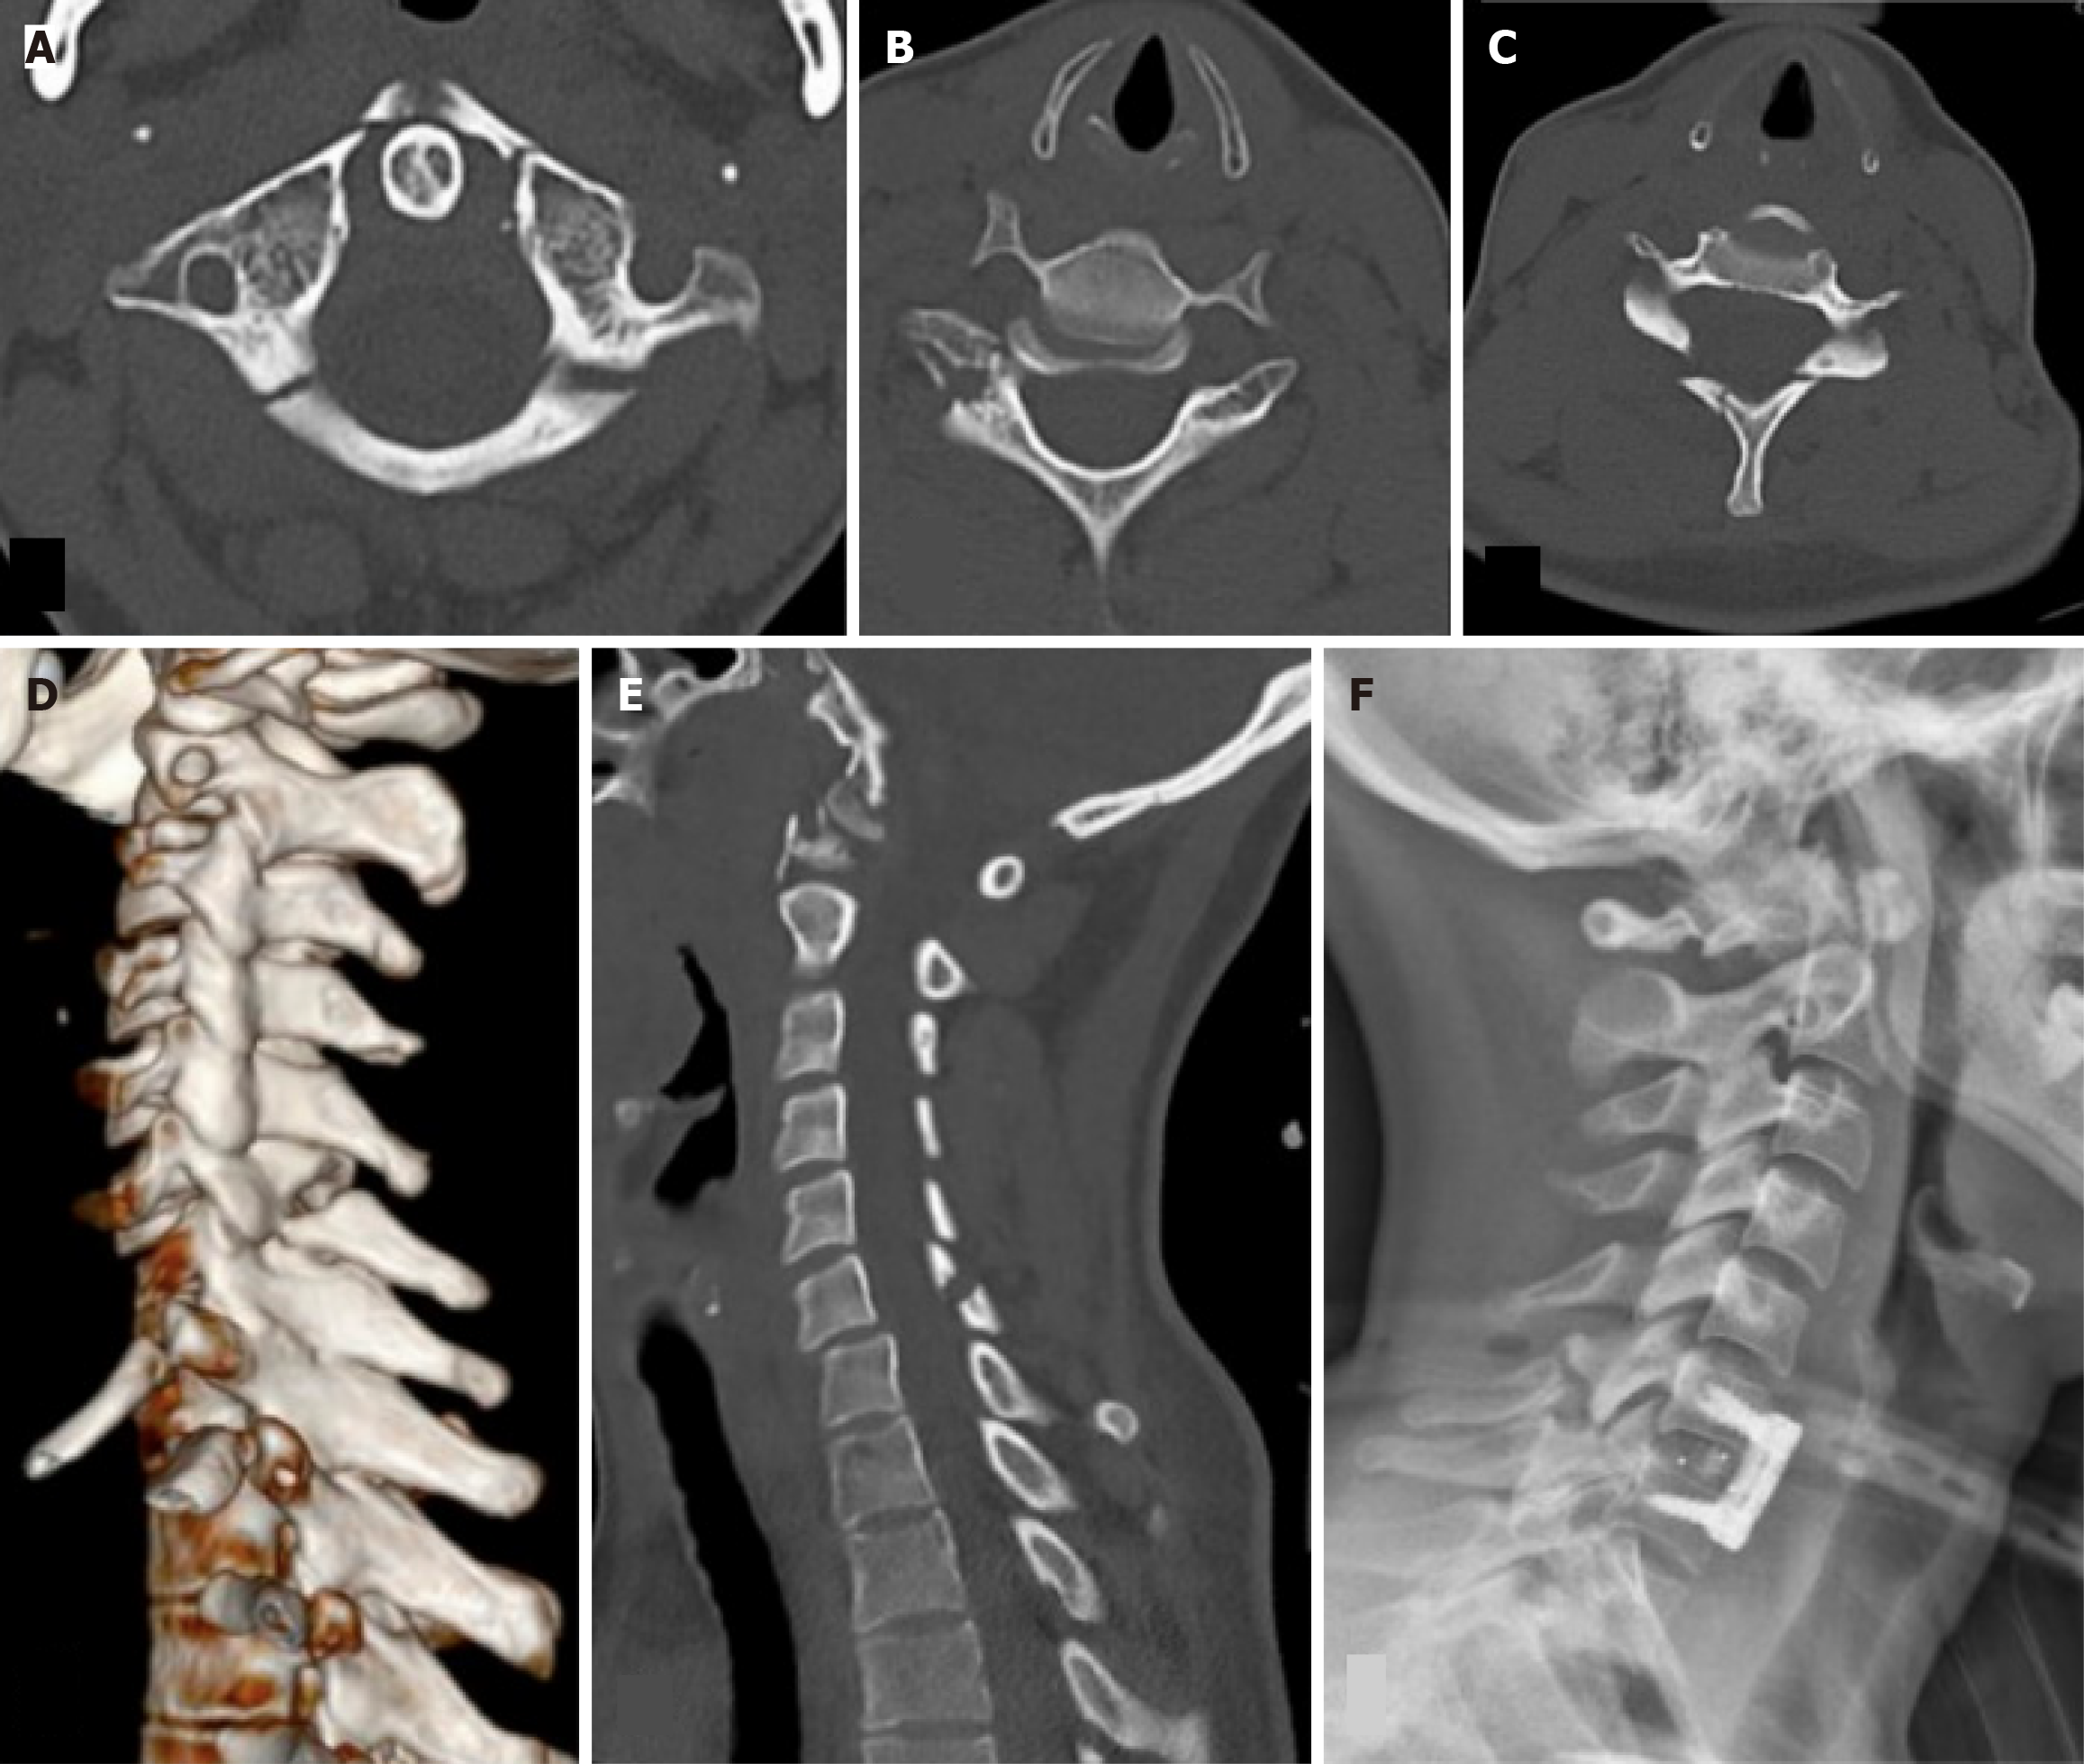

Case 2: Pan CT scan revealed a complex, multi-level injury pattern consistent with a high-energy rollover ejection. She sustained a Jefferson fracture (type III) of the Atlas (C1), bilateral facet joint fractures at C6-C7 with grade 1 spon

Initially, she was managed with a halo vest for the Jefferson fracture and subsequently underwent anterior cervical discectomy and fusion (ACDF) at C6-C7 (Figure 2) ten days after admission. This combination of biomechanical mechanisms explains the instability and the need for surgical stabilization, unlike the relatively stable Jefferson fracture, which is managed conservatively with a halo vest.

Facet dislocation: The dislocation of the facet occurs when the flexion/distraction force, along with the rotatory force, is applied to the cervical spine. The inferior articular facet of the upper cervical level moves over the superior articular facet of the lower cervical level. It can be unilateral or bilateral and usually affects the C4-C5 or C5-C6 levels. The patient often presents with radiculopathy of an existing nerve root. Unilateral injuries are more stable than bilateral facet injuries. Bilateral facet dislocation is usually associated with spinal cord injury because of the anterolisthesis of the vertebral body. These injuries can be managed with axial in-line traction and some cervical spine flexion. Close reduction should be abandoned if neurological symptoms worsen. In the present series, case two had a bilateral facet joint fracture at the C6-C7 level with grade 1 spondylolisthesis of C6 over C7, with a fracture extending to the posterior elements of C6. This patient was managed with ACDF (Figure 2). Another patient (case three) had a right C6-C7 facet joint fracture and was managed conservatively with a stiff collar.

C1 fracture: The fracture of the atlas constitutes about 2%-13% of all cervical spine injuries and is typically associated with the traumatic axial loading of the head on the lateral masses of C1[15]. This type of injury causes Jefferson fractures, a burst-type fracture of C1 with bilateral fractures of the anterior and posterior arches of the atlas. Other external forces can be applied during this type of fracture, which includes flexion, extension, and rotatory forces. Sometimes, the isolated anterior or posterior arch fractures or a unilateral lateral mass fracture can occur, depending on the combination of forces applied concomitantly with the axial compression[16]. The treatment of this fracture depends on the mechanical stability and neurological status. If the transverse ligament is intact, the injury can be managed with a stiff collar or halo immobilization. If the ligament is injured, treatment will include a C1-C2 fusion or an occipito-cervical fusion. Two of our patients (cases two and three), who were unrestrained back-seat passengers, sustained a Jefferson fracture along with other cervical spine injuries (Figures 2 and 4). Both patients had no neurological deficit and were managed with a halo vest application.